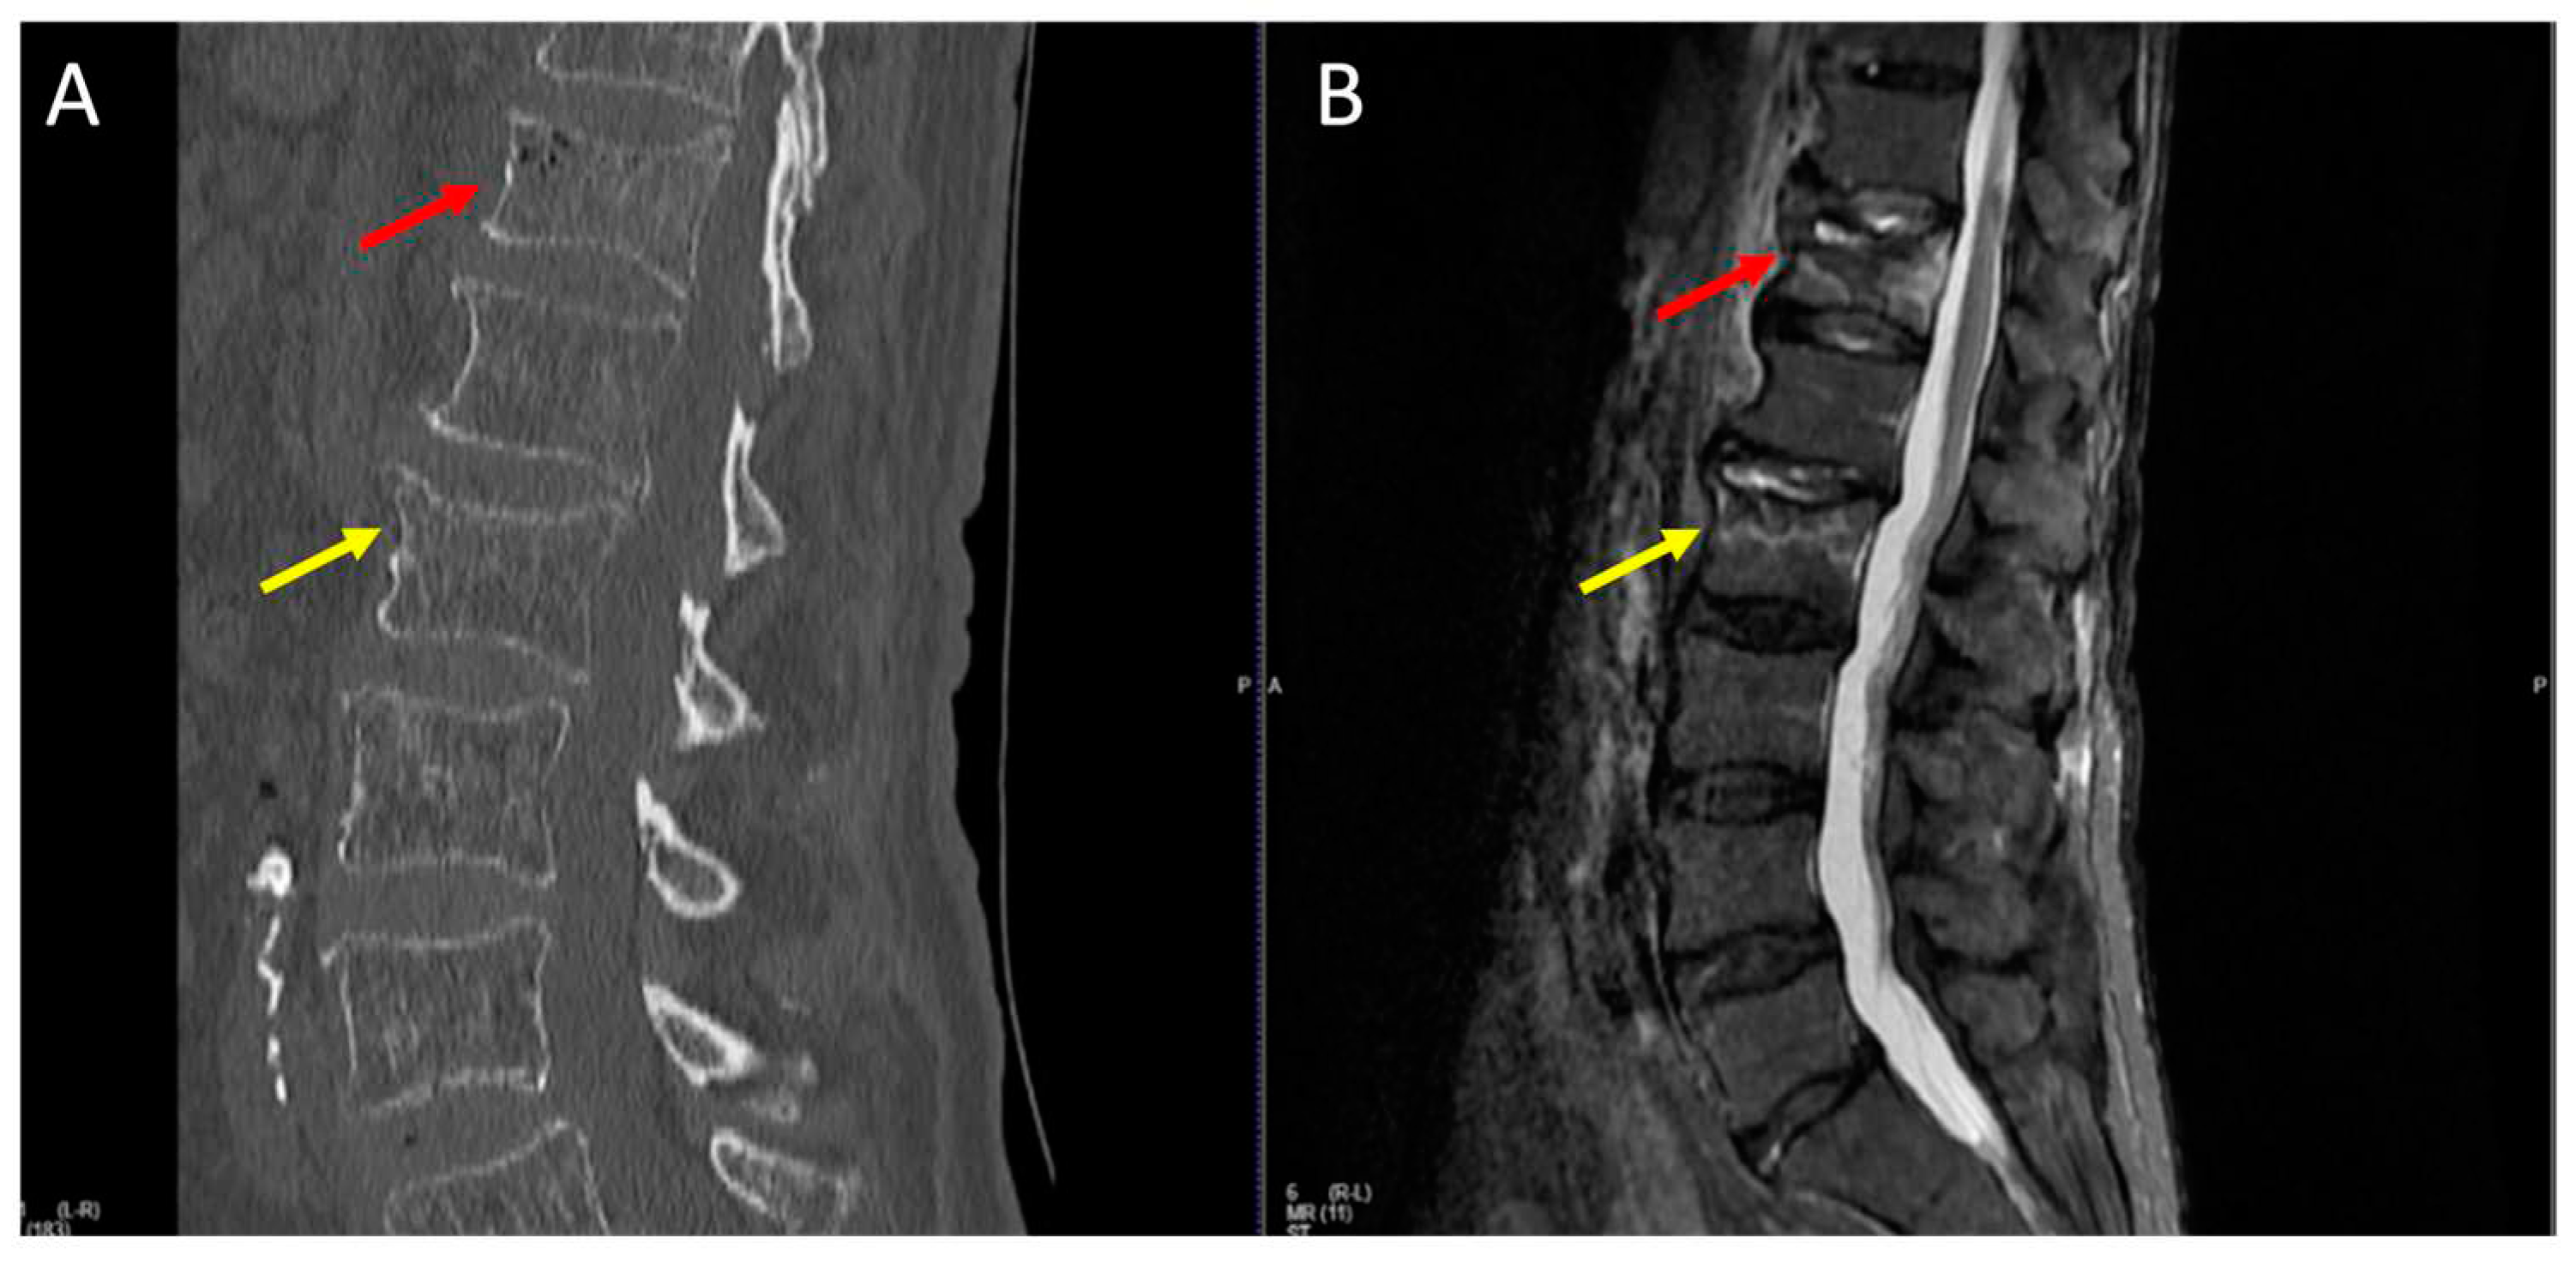

Figure 1. A CT scan displays a barely noticeable fracture of the ThXII vertebra (A). On the MRI STIR sequence, the ThXII vertebra fracture is more distinctly visible, also uncovering a previously undetected fracture of the LII vertebra (B). Red and yellow arrows show ThXII and LII vertebrae, respectively.